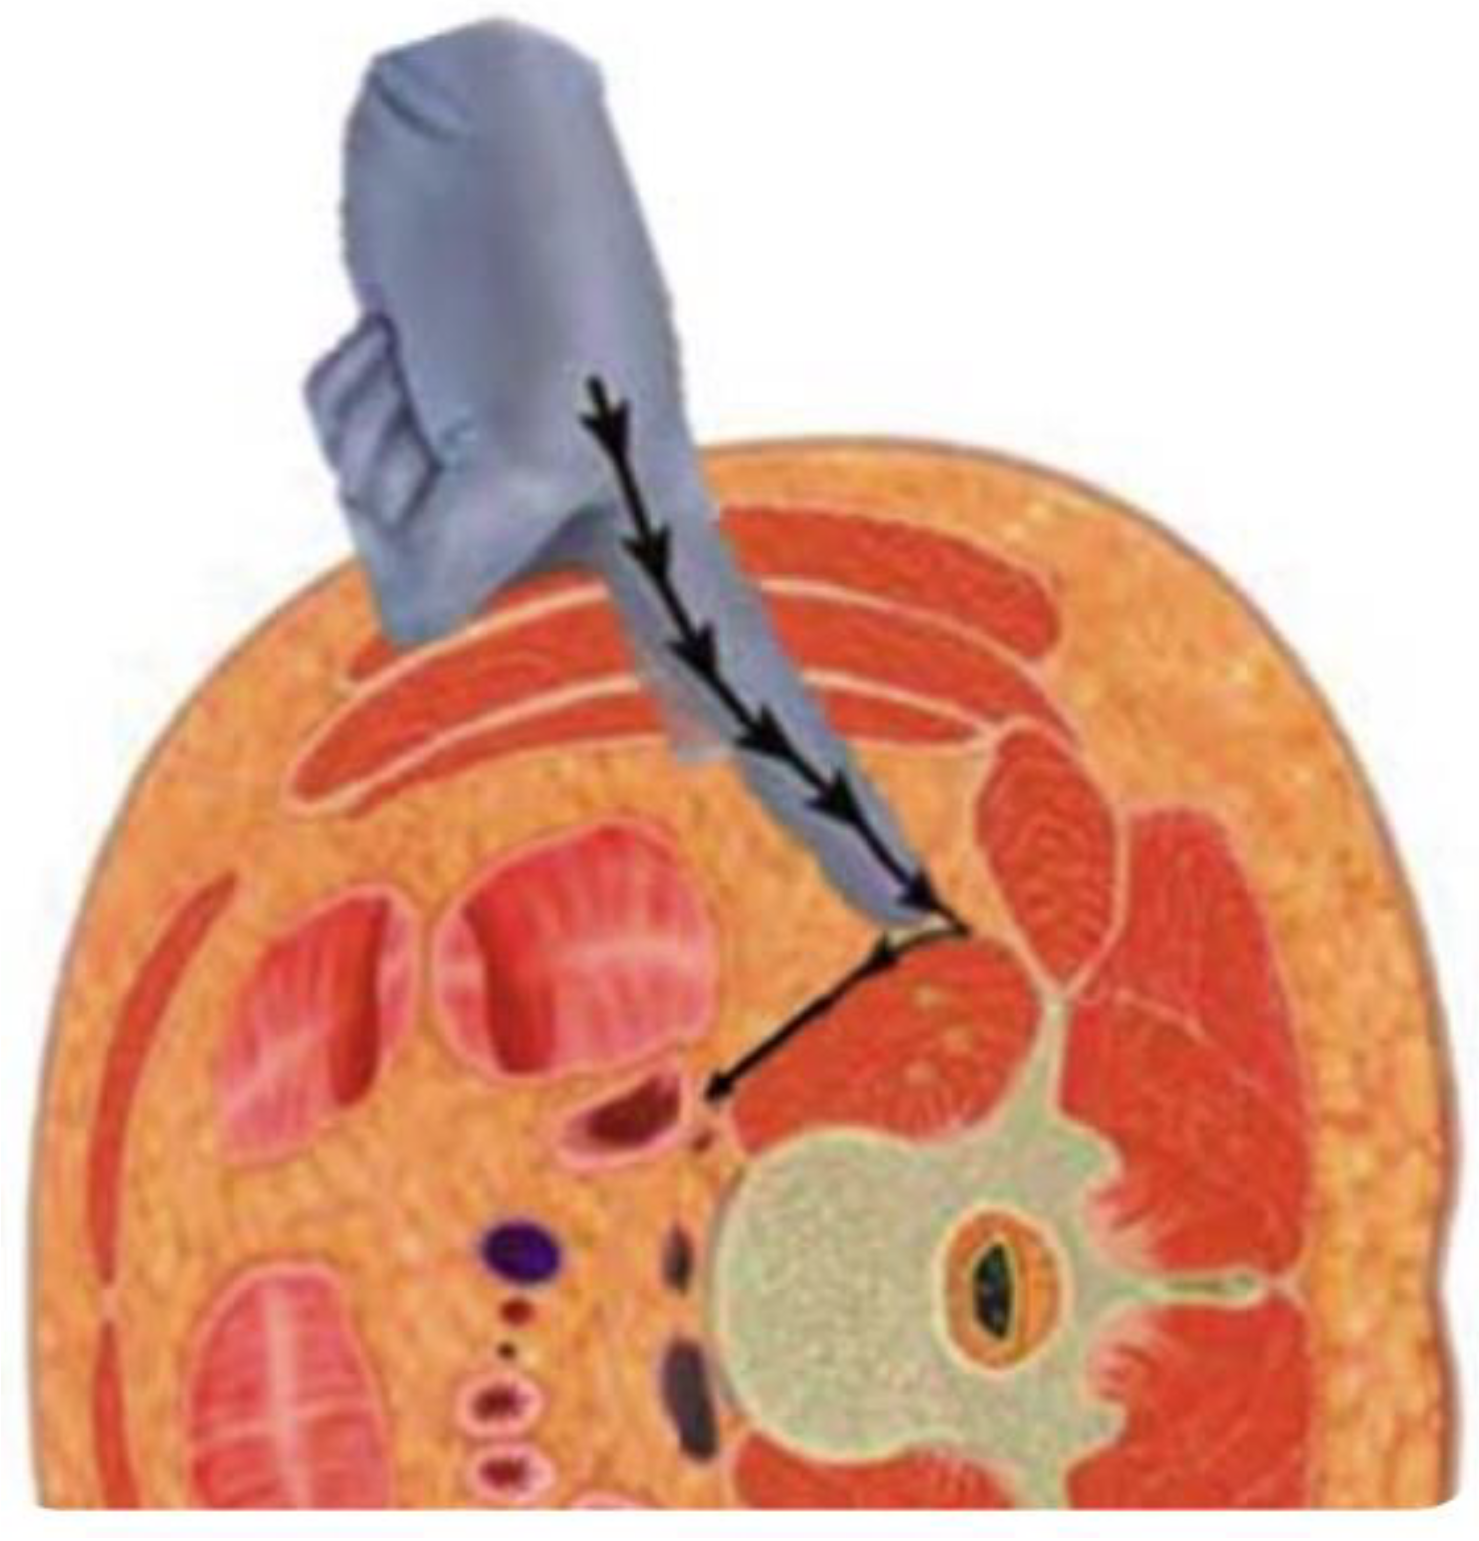

- Epstein, N.E. Review of Risks and Complications of Extreme Lateral Interbody Fusion (XLIF). Surg. Neurol. Int. 2019, 10, 237. [Google Scholar] [CrossRef] [PubMed] [PubMed Central]

- Li, J.X.; Phan, K.; Mobbs, R. Oblique Lumbar Interbody Fusion: Technical Aspects, Operative Outcomes, and Complications. World Neurosurg. 2017, 98, 113–123. [Google Scholar] [CrossRef] [PubMed]

- Yagi, M.; Fujita, N.; Hasegawa, T.; Inoue, G.; Kotani, Y.; Ohtori, S.; Orita, S.; Oshima, Y.; Sakai, D.; Sakai, T.; et al. Nationwide Survey of the Surgical Complications Associated with Lateral Lumbar Interbody Fusion in 2015-2020. Spine Surg. Relat. Res. 2022, 7, 249–256. [Google Scholar] [CrossRef] [PubMed] [PubMed Central]